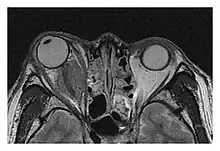

The extent of inflammation that can occur in IgG4-ROD is well demonstrated on magnetic resonance imaging (MRI).

Enlargements in the left inferior rectus muscle and infraorbital nerve (arrow) in a 65-year-old man with a serum IgG4 of 404 mg/dL.[1] (T2-weighted MRI)